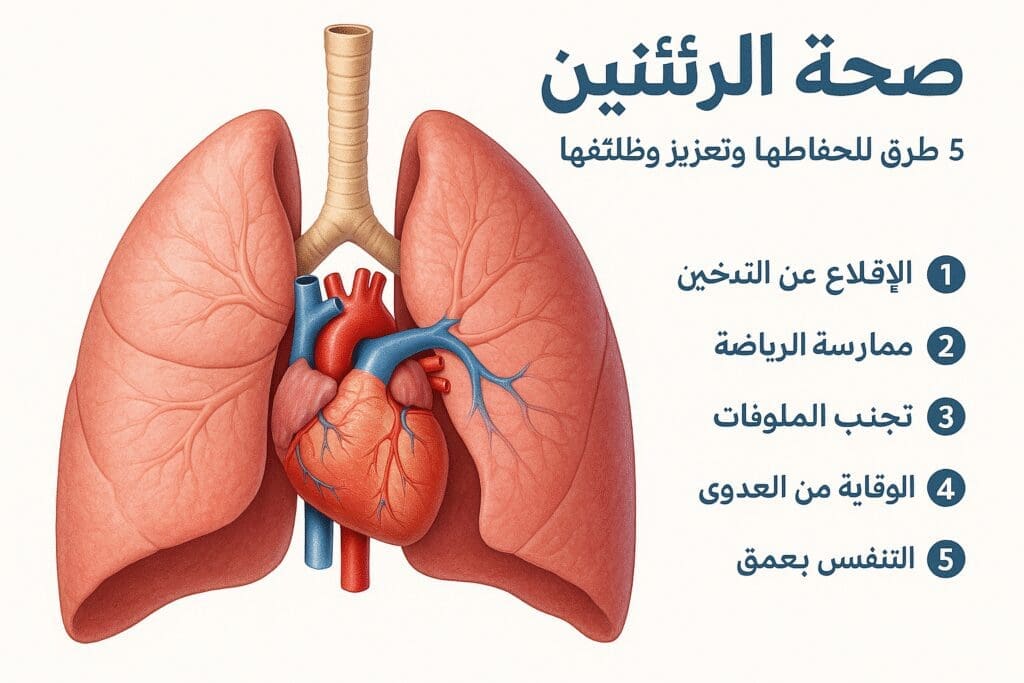

مقالات طبية من مساهمات الأطباء